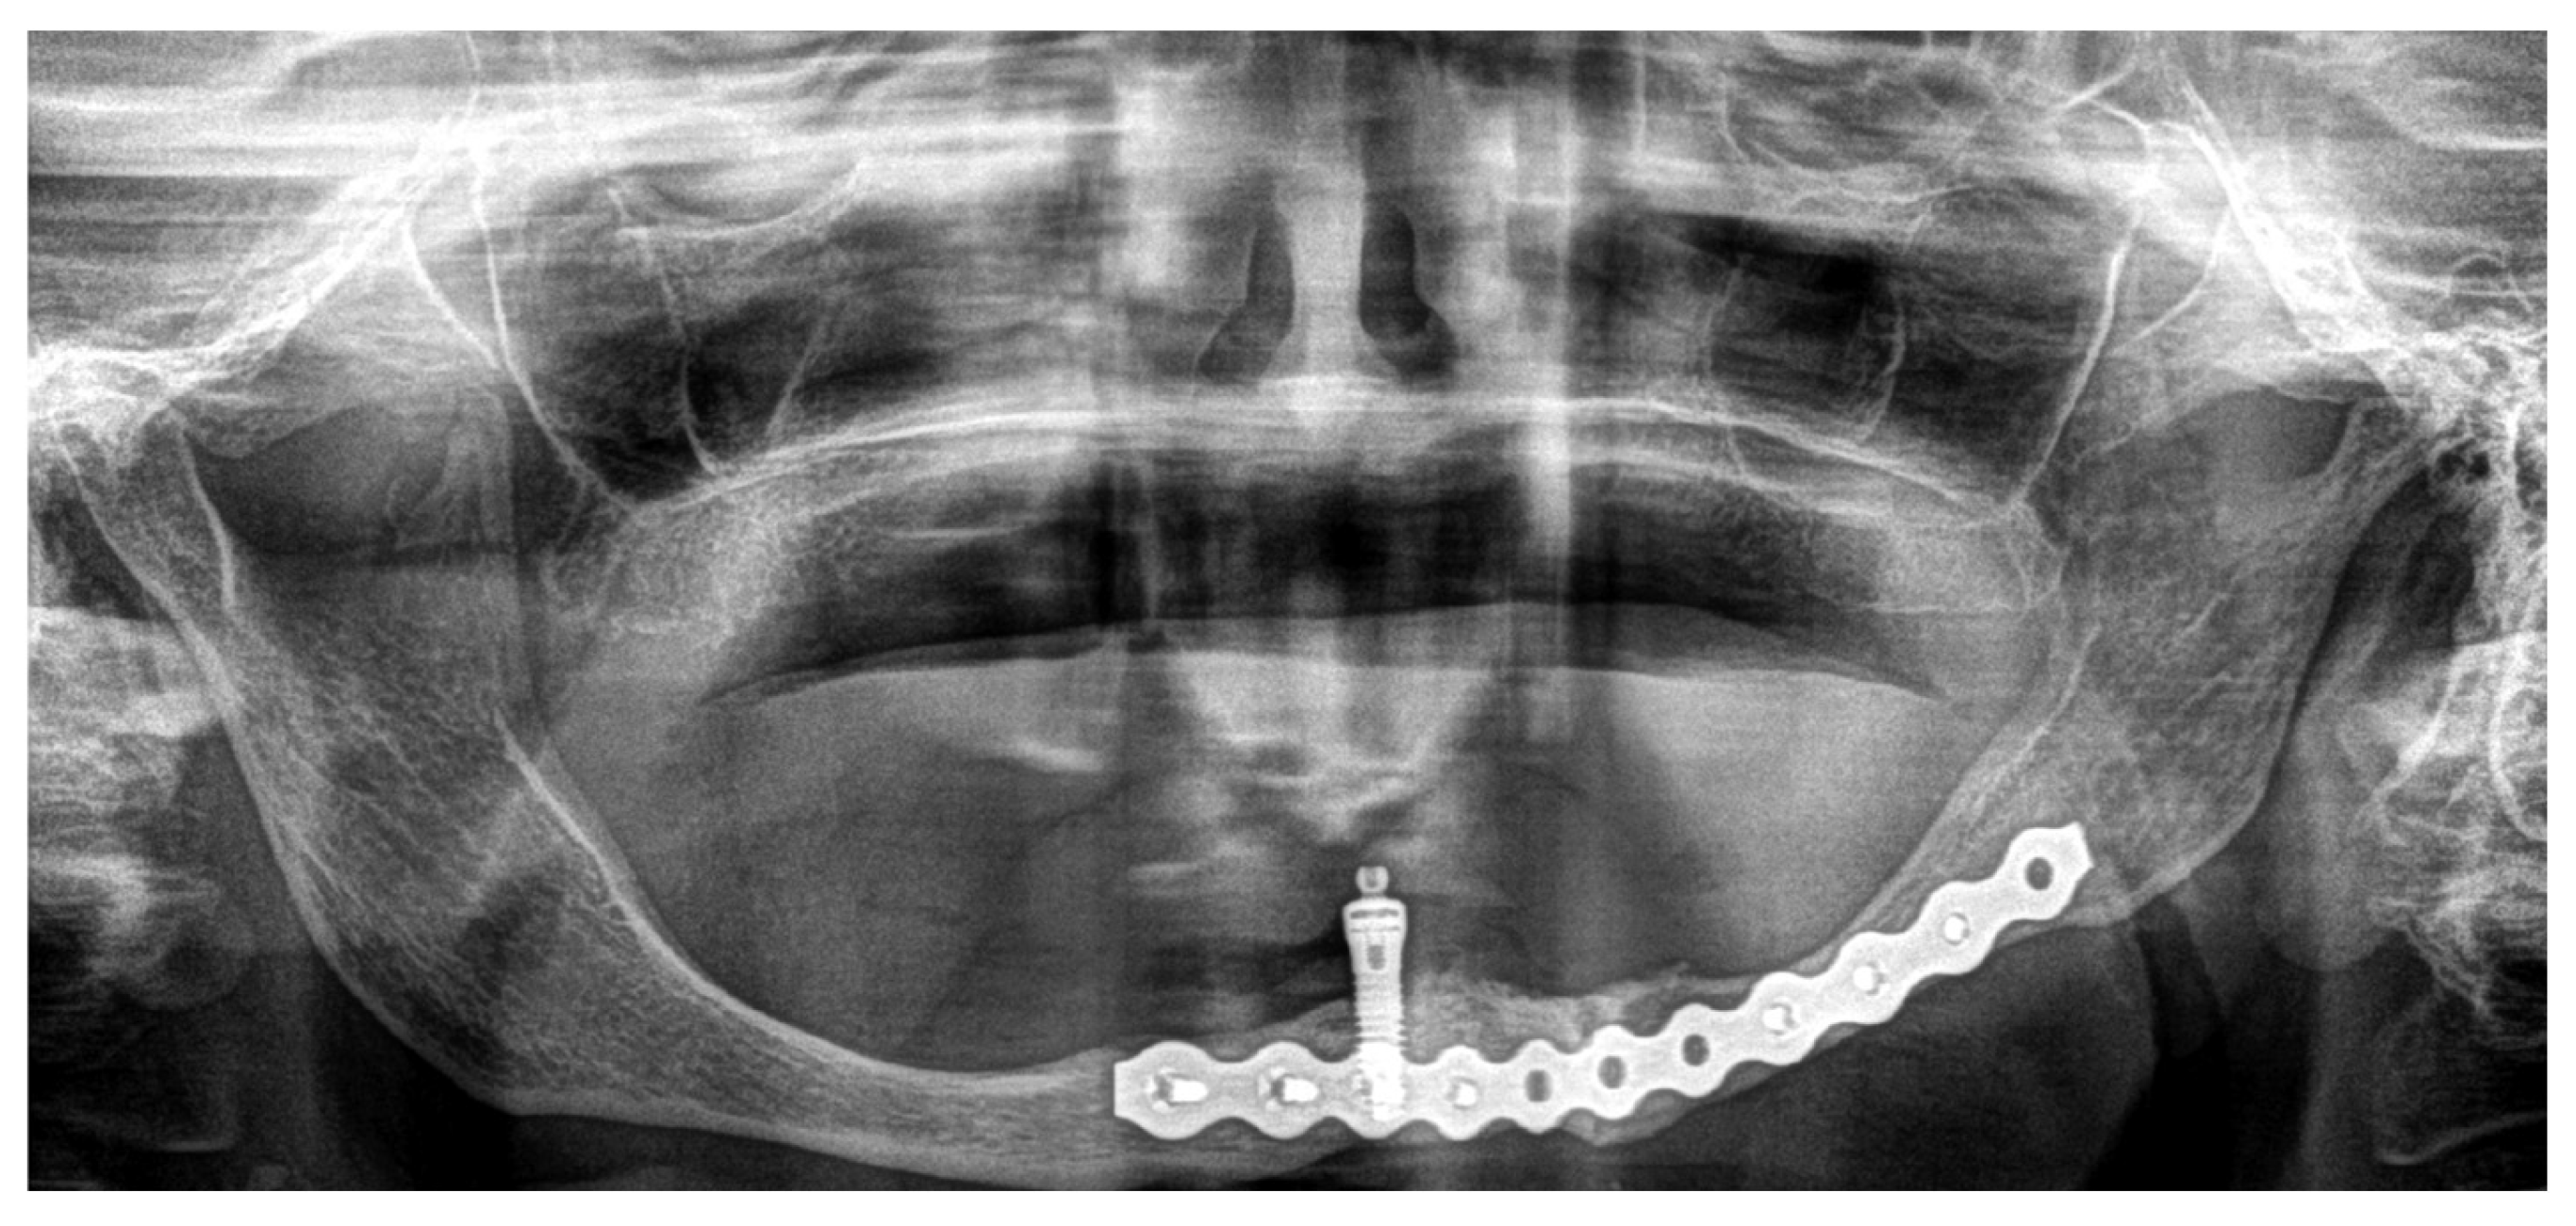

3.1. Case 1

3.2. Case 2

| Type of internal fixation | 2.5 mm thick mandibular locking plate with 2.4 mm screw diameter | 3 (50%) |

| 2.0 mm thick mandibular locking plate with 2 mm screw diameter + 1.0 mm thick mandibular plate with 2 mm screw diameter | 1 (16.67%) | |

| 2.0 mm thick mandibular locking plate with 2 mm screw diameter + titanium mesh | 1 (16.67%) | |

| Use of bone grafts | Non-bone graft | 3 (50%) |

| Autologous graft (iliac crest) | 1 (16.67%) | |

| Autologous graft (mandibular ramus) | 1 (16.67%) | |

| Non-autologous graft | 1 (16.67%) | |